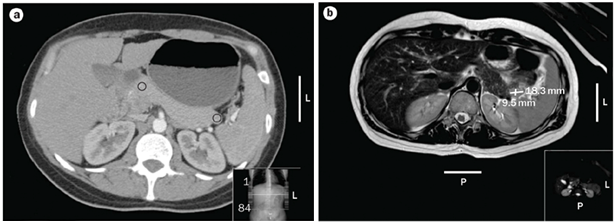

The latest studies have demonstrated that MRI is superior to other preoperative imaging techniques in identifying small pancreatic insulinoma. Its sensitivity ranges from 85% to 95%, in the detection of insulinoma and the determination of the presence of metastases. Using conventional sequences, small insulinoma usually have a low signal on T1-weighted sequences and a high signal on T2-weighted sequences. Some insulinomas containing fibrous tissue may show low signal intensity on both T1- and T2-weighted images. An improvement in MRI technique is the use of diffusion weighted MRI (DWI-MRI) for abdominal imaging. DWI is an MRI technique that detects changes in the molecular diffusion of water in biologic tissues and the valuable role of DWI in the detection of pancreatic tumors has been reported in several studies (Figure 4A), (Figure 4B) & (Figure 5).33–36

Figure 4 Localization of a possible insulinoma in the case patient. (a) CT scan of the abdomen of the patient described showing nodular pancreas but no differential enhancement after contrast (b) | MRI scan of the abdomen showing a 18.3mm by 9.5mm enhancing islet cell tumor within the tail of the pancreas. 31